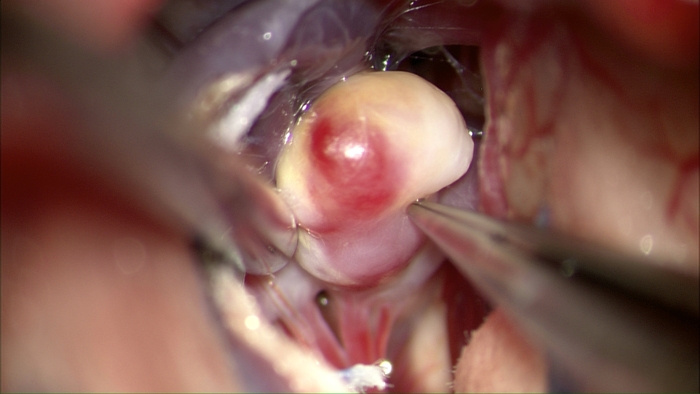

뇌동맥류(Cerebral aneurysm)를 치료하는 방법이다. 뇌동맥류는 뇌동맥의 일부가 풍선처럼 부푼 병변을 지칭하며 전체 유병률은 약 2-4% 정도로 알려져 있는 비교적 흔한 질병이다. 뇌동맥류는 치명적인 거미막하출혈(지주막하출혈, Subarachnoid hemorrhage)의 주요 원인이며, 대부분의 뇌동맥류는 평소 아무런 증상을 유발시키지 않다가 갑자기 파열되기 때문에 주의를 요한다. 뇌동맥류는 현재까지 효과적인 약물요법이 없어 필요한 경우 수술적으로 치료를 해야 한다. 동맥류 치료에서 가장 중요한 원칙은 동맥류를 소멸(Obliteration)시켜 파열되지 않게 함과 동시에 정상 혈류를 보존하여 뇌조직이 손상되지 않도록 하는 것이다. 뇌동맥류의 수술 방법은 크게 개두술을 통한 수술적 결찰술(Surgical clipping)과 혈관내 접근을 통한 색전술(Endovascular coiling 또는 coil embolization)로 나뉜다. 뇌동맥류 수술은 좁은 의미에서는 개두술적 결찰술을 지칭하지만, 넓은 의미에서는 혈관내 접근법까지 포함하여 지칭한다. 이 글에서는 주로 개두술적 결찰술에 대해 기술한다. 수술적 결찰술은 동맥류 경부 결찰술(Aneurysm neck clipping) 또는 동맥류 결찰술 등으로도 표기되며, 1937년 최초 시행된 이후 현재까지 기구와 술기가 꾸준히 발전하여 왔다. 특히 광학기술과 재료공학의 발달로 과거에 비하여 수술의 성적이 향상되었다. 수술적 결찰술의 장점은 색전술에 비하여 내구성이 우수하여 수술 후 재발이 적고 추적검사의 필요 빈도가 낮아 젊은 연령에서 유리하다는 점, 수술 후 약물 치료가 필요 없다는 점 등을 들 수 있다. (그림) 수술현미경시야에서 노출된 중대뇌동맥 분지부에 발생한 동맥류: 동맥류 벽이 염증성 반응으로 인하여 노란색으로 변성이 되었다. 주변 혈관을 확보하고 미세 분지를 확인한 뒤 동맥류 결찰을 시행한 뒤의 모습이다.

노출된 뇌동맥류

결찰

추가결찰